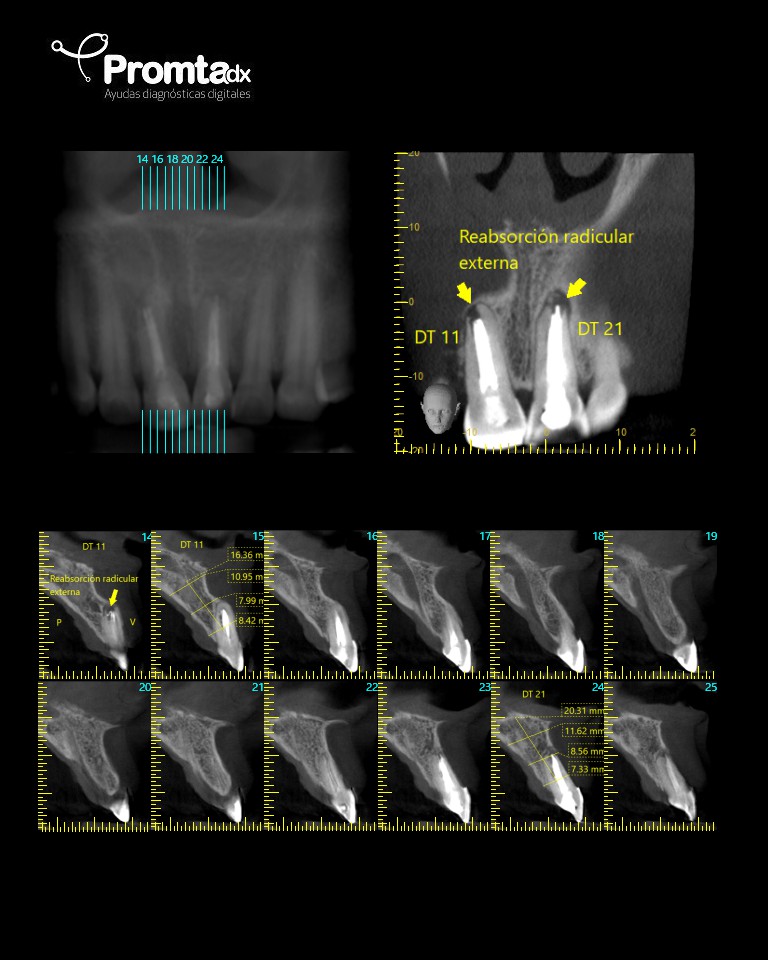

- CBCT: La tomografía computarizada de haz cónico es una imagen en 3D que proporciona imágenes de alta resolución del complejo craneofacial. Permite evaluar la cantidad y calidad ósea para la colocación de implantes dentales, adicionalmente es útil para la evaluación de dientes incluidos, fracturas y reabsorciones radiculares, entre otros.

La tomografía computarizada de haz cónico (CBCT) proporciona imágenes en 3D de alta resolución del craneofacial, ideal para planificar implantes, evaluar dientes incluidos, fracturas y reabsorciones radiculares.